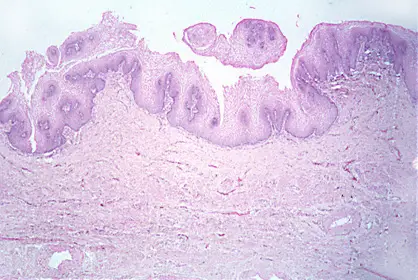

VAGINA DE UNA MUJER JOVEN

La vagina de la mujer joven se caracteriza por tener una gran cantidad de capas celulares muy espesas.